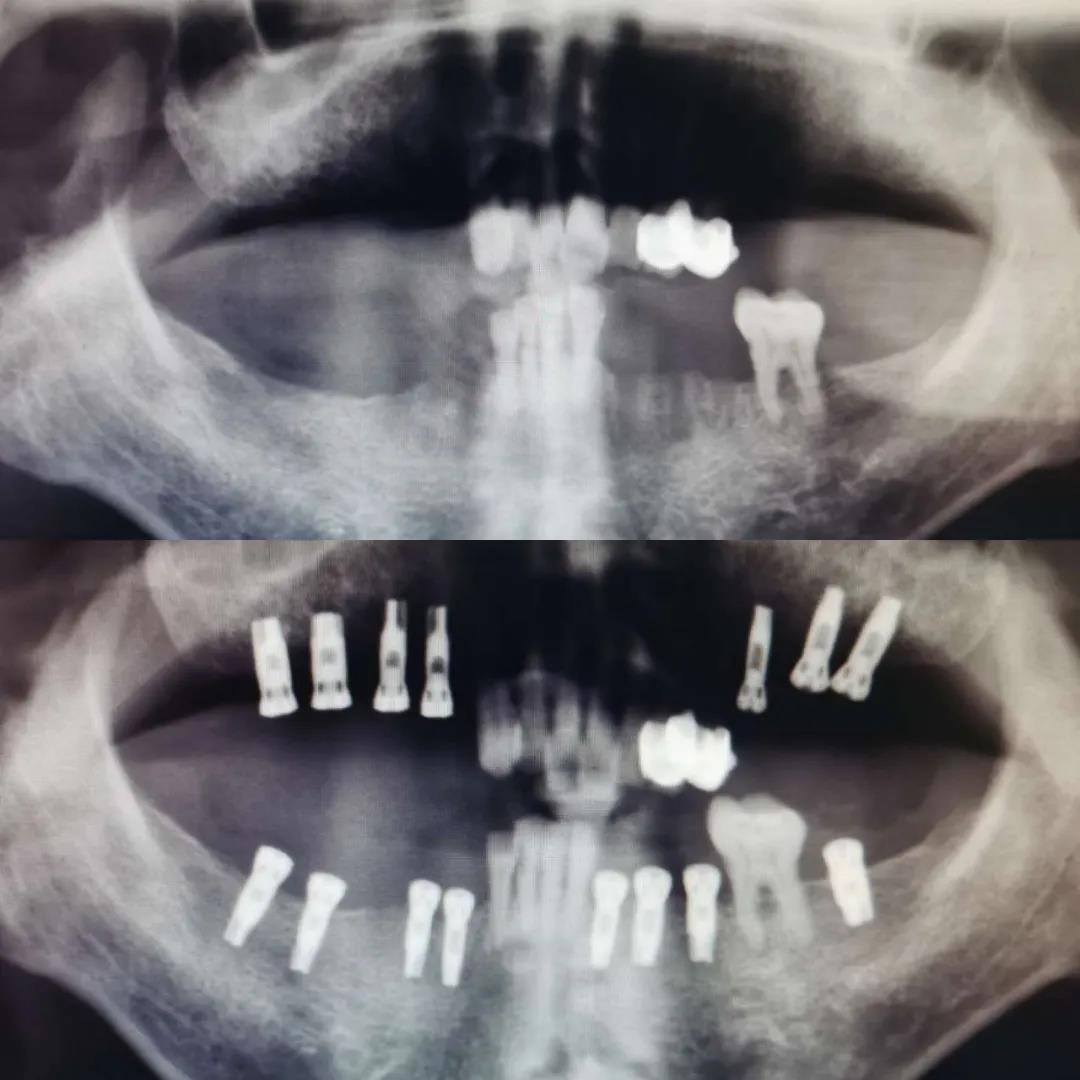

此次培訓(xùn)是由美國(guó)哈佛大學(xué)牙學(xué)院博士張杰發(fā)起,江陰金泰克生物技術(shù)有限公司舉辦的。張杰博士和山西省口腔醫(yī)學(xué)會(huì)副會(huì)長(zhǎng)鄭強(qiáng)教授、金泰克旗下門診醫(yī)師張乙云共同為學(xué)員們呈現(xiàn)了一場(chǎng)精彩的口腔學(xué)術(shù)盛宴。種植技術(shù)示范現(xiàn)場(chǎng),鄭強(qiáng)教授和張乙云醫(yī)師一小時(shí)內(nèi)為患者種植牙15顆,現(xiàn)場(chǎng)觀摩學(xué)員無(wú)不對(duì)金泰克種植體系統(tǒng)先進(jìn)的設(shè)計(jì)原理和簡(jiǎn)易的操作方法表示稱贊。

(學(xué)員現(xiàn)場(chǎng)觀摩鄭強(qiáng)教授手術(shù)示范,一小時(shí)內(nèi)完成15顆種植牙)

手術(shù)過(guò)程時(shí)間持續(xù)一個(gè)小時(shí),患者缺失的主要為后牙部分,情況復(fù)雜,難度較高,術(shù)后無(wú)不適狀況,面部無(wú)腫痛。